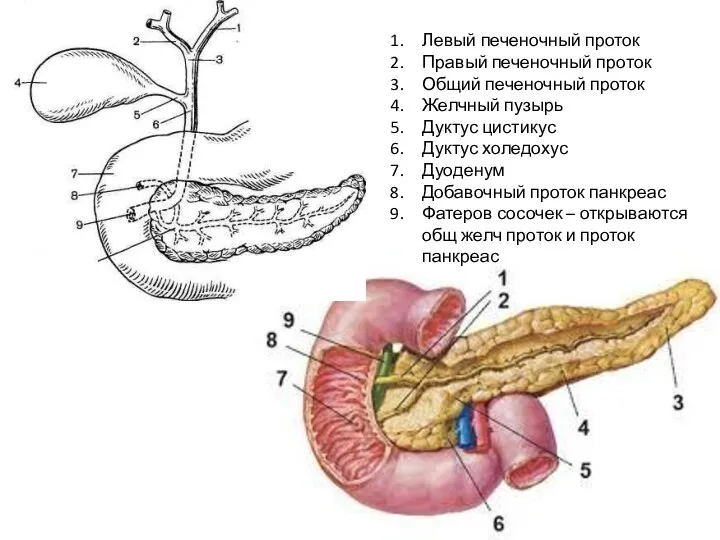

Анатомия и особенности Гартманова кармана желчного пузыря